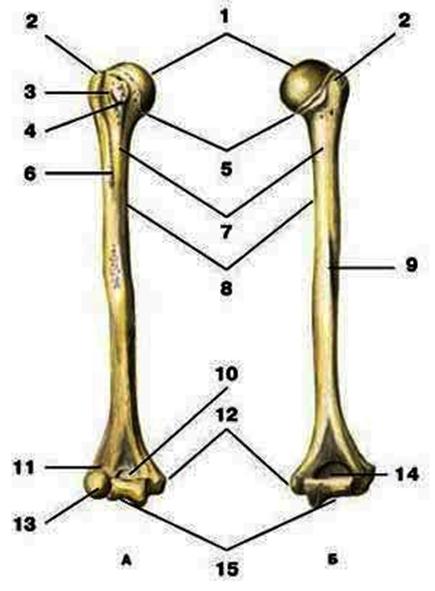

V2:Тема 1.3 Кости верхней конечности и их соединения

S: Цифра 1 обозначает … плечевой кости.

+:сaput

-:t uberculum majus

-:troсhlea

-:capitulum

-:epicondylus lateralis

S: Число 15 обозначает... плечевой кости.

+:trochlea

S: Цифра 5 указывает на...плечевой кости.

+:collum anatomicum

-:collum chirurgicum

S: Число 10 обозначает... плечевой кости.

+:fossa coronoidea

S: Число 14 указывает на... плечевой кости.

+:fossa olecrani

S: Цифра 9 указывает на... плечевой кости.

+:sulcus nervi radialis

S: Число 12 обозначает... плечевой кости.

+:epicondylus medialis